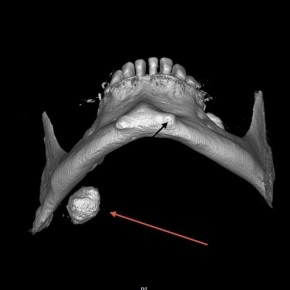

Слюнной камень растил приморец 17 лет.

Врачи Краевой больницы №2 во Владивостоке удалили из слюнной железы мужчины камень диаметром более 2 сантиметров. Он болел слюнно-каменной болезнью 17 лет, но к врачам обратился, когда камень уже стал "сказываться на качестве жизни".

Фото: Telegram-канал ККБ №2.